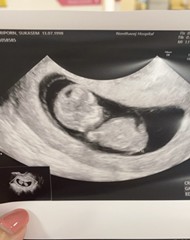

12 มกรา 66 ค่ะ ท้องแบบไม่รู้ตัว รู้อีกทีก็มาแบบในภาพแล้ว

บ้านนี้ไปซาวด์ตอน7สัปดาห์